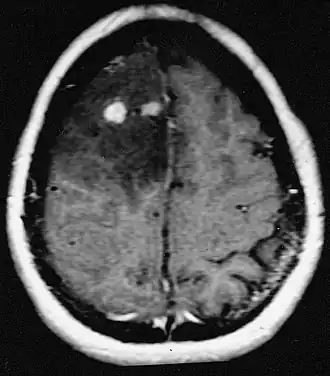

Le lymphome primitif du système nerveux central représente environ 2 pour cent à 3 pour cent de toutes les tumeurs cérébrales chez les patients ayant un système immunitaire normal. Ils surviennent plus fréquemment chez les hommes de plus de 55 ans jusqu'à 60 ans. Près de la moitié de tous les lymphomes surviennent chez des patients de plus de 60 ans et environ un quart chez des patients de plus de 70 ans. L'incidence semble augmenter avec l'âge, mais la raison n'est pas encore claire. Les patients dont le système immunitaire est affaibli sont plus à risque de développer un lymphome du SNC, de sorte que ceux qui ont subi une greffe d'organe ont une immunodéficience congénitale ou une maladie auto-immune, ou sont infectés par le virus de l'immunodéficience humaine. Les lymphomes cérébraux associés au VIH sont associés au virus d'Epstein-Barr, en particulier chez les patients dont le nombre de lymphocytes CD4 est inférieur à 500 cellules par millimètre cube dans le sang. La plupart des lymphomes du SNC sont des lymphomes diffus à grandes cellules B.

Les patients souffrent d'une variété de symptômes caractéristiques d'une lésion massive focale ou multifocale. L'IRM montre généralement des tumeurs avec un rehaussement de contraste homogène au sein de la substance blanche périventriculaire profonde. La multifocalité et le rehaussement inhomogène sont typiques des patients dont le système immunitaire est affaibli. L'analyse du lymphome du SNC est extrêmement importante dans le diagnostic différentiel de la néoplasie cérébrale. Il est à noter que l'administration de corticoïdes peut entraîner la disparition complète du rehaussement, rendant difficile le diagnostic des lésions. Par conséquent, si un lymphome du SNC doit être pris en compte dans le diagnostic différentiel, les corticoïdes doivent être évités à moins que l'effet de masse ne provoque un problème grave et immédiat chez le patient.